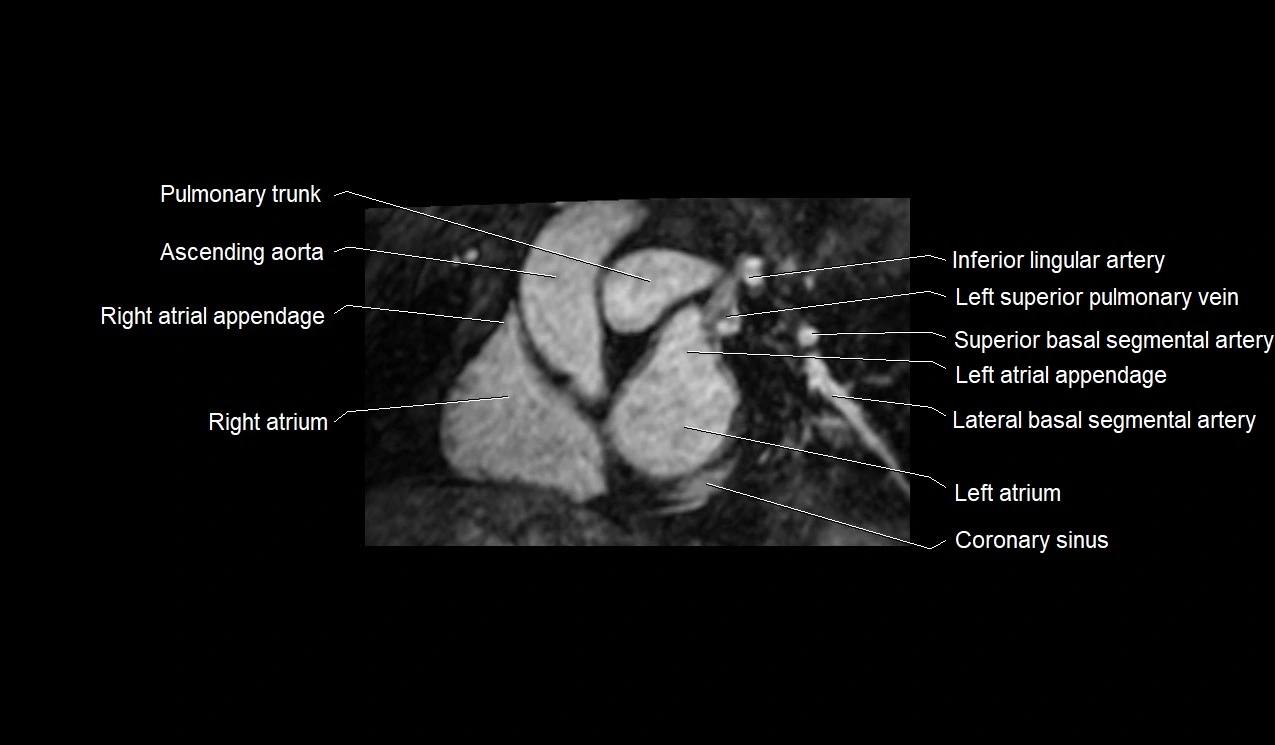

MRI image